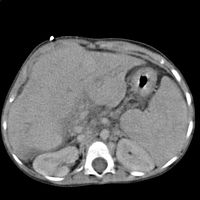

Pojmem pomocná vyšetření (nověji a přiléhavěji též paraklinická vyšeření) indikuje lékař, když potřebuje potvrdit diagnózu, stanovit rozsah choroby nebo stále častěji i při záchytu choroby ještě před jejím propuknutím v rámci preventivních prohlídek. Patří sem celá řada metod biochemických, imunologických , mikrobiologických, histologických, endoskopických, radiologických a dalších. V praxi se obvykle používá jakou základní vyšetření na interním oddělení RTG hrudníku, krevní obraz, základní biochemie krve (sodík, draslík, glukóza, močovina, kreatinin, kyselina močová a cholesterol), základní biochemie moči testačním proužkem (glukóza, žlučová barviva, krev a bílkoviny). Důležitou roli v rozhodování o indikaci pomocné vyšetřovací metody hrají i další faktory, především cena vyšetření a zátěž pacienta radioaktivním zářením.